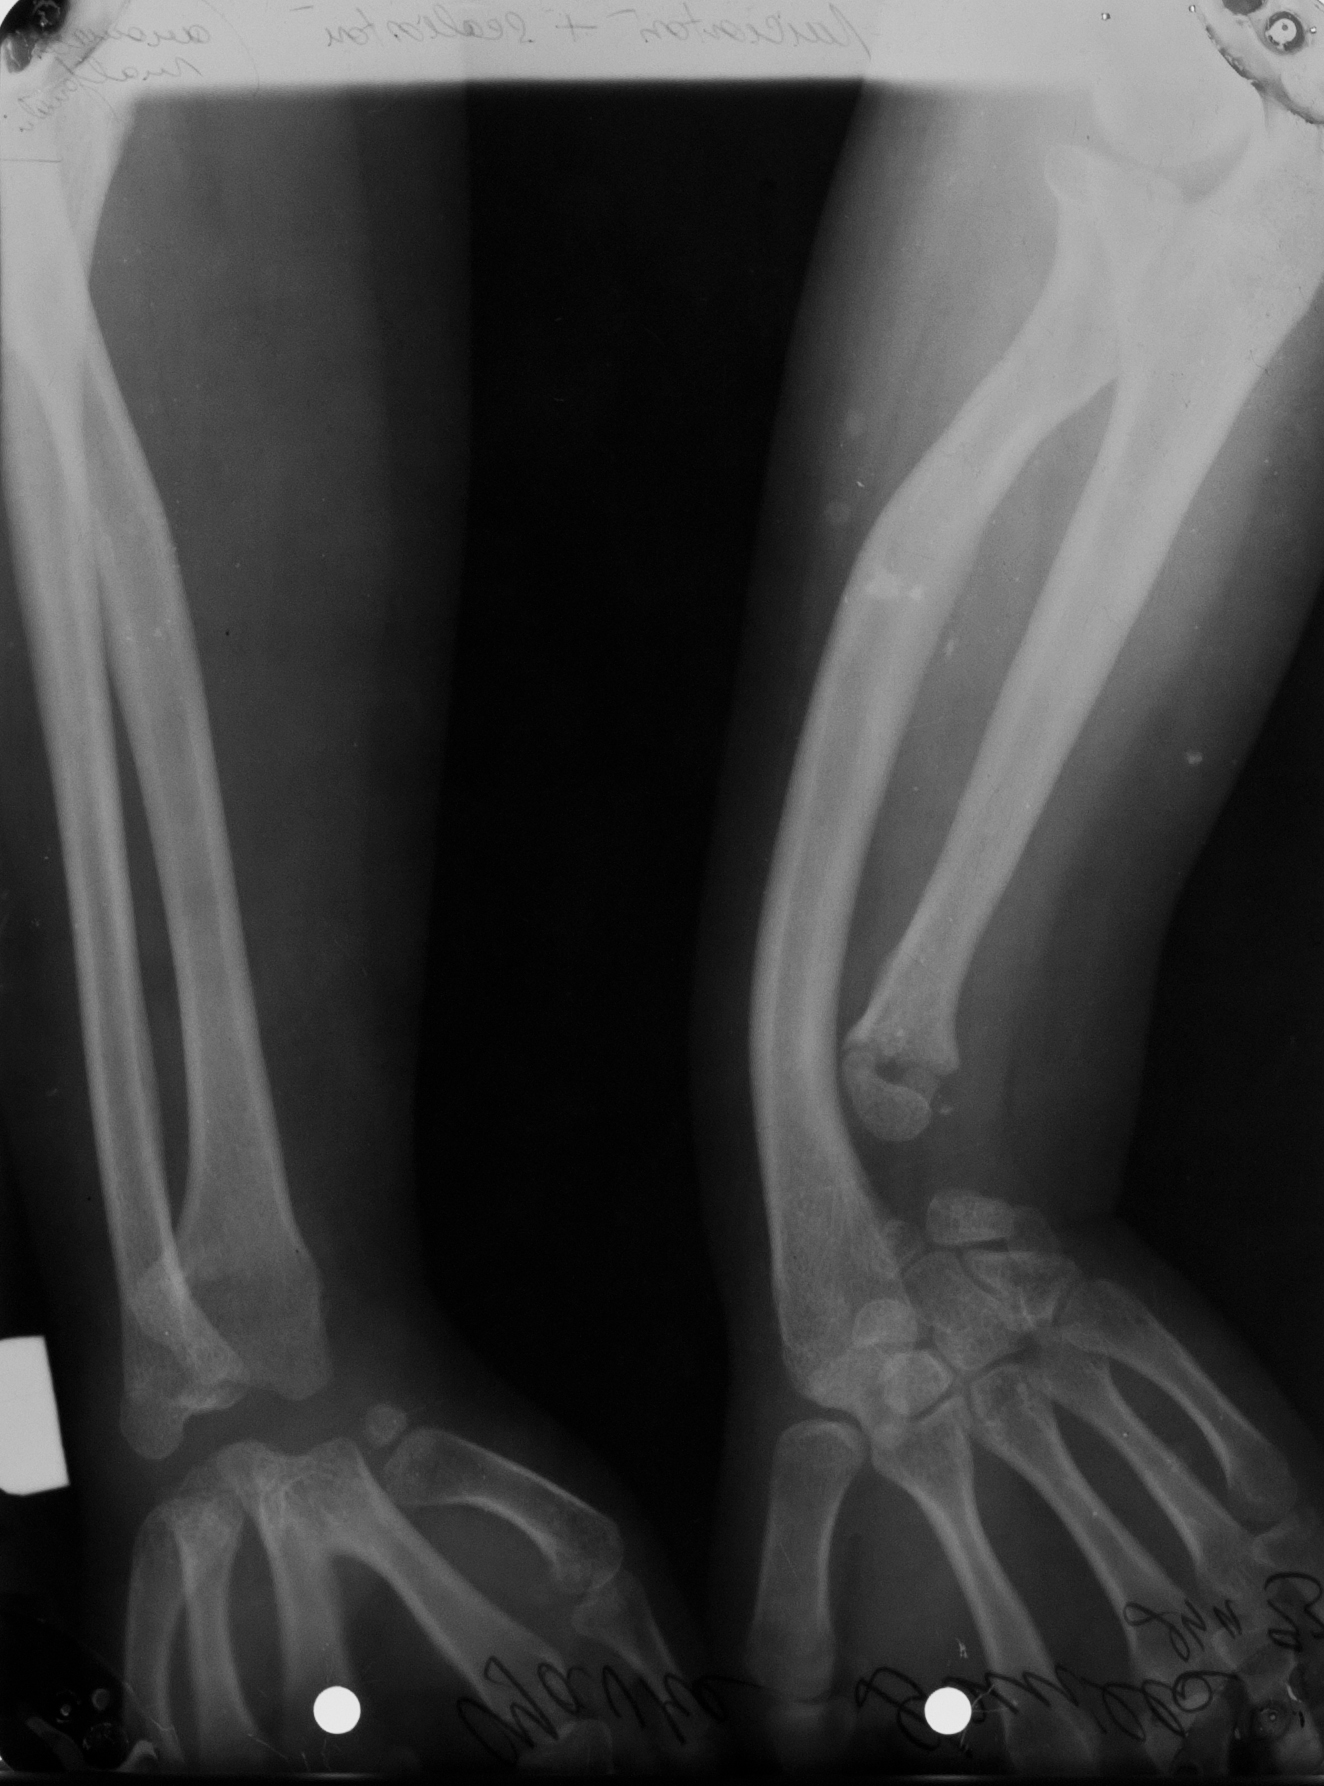

FOCOMELIE

Hipoplazie ulnara, agenezie de radius

SCOLIOSTOZA DE RADIUS STANGA, HIPOPLAZIE ULNARA STANGA, AGENEZIA OASELOR CARPIENE DREAPTA